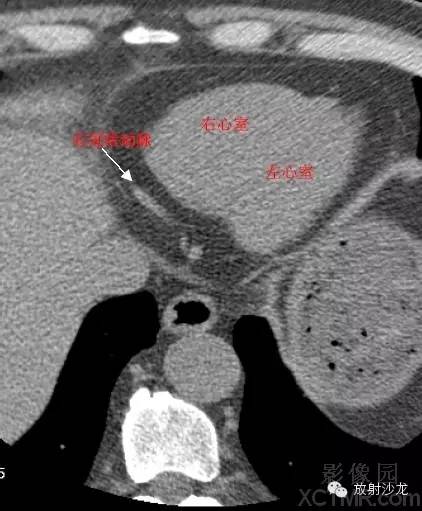

LV -Left Ventricle左心室

RV -Right Ventricle右心室

RCA -Right Coronary Artery 右冠状动脉